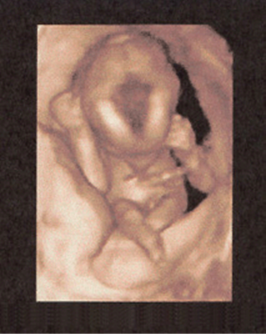

Three-dimensional sonography offers a detailed depiction of the fetal face, extremities, outer contours, and certain organs such as the fetal heart, brain, liver, kidneys, and spine (Figs. 8–4 through 8–27). Depiction of the fetus with 3D sonography has gained widespread and universal demand. However, there should be clinical indication for such studies since any unnecessary exposure to ultrasound (see the American Institute of Ultrasound in Medicine statement regarding use of 3D ultrasound for “entertainment”) should be avoided.

FIGURE 8–9. Three-dimensional sonogram of face of 20-week fetus. (Courtesy of Philips Healthcare.)